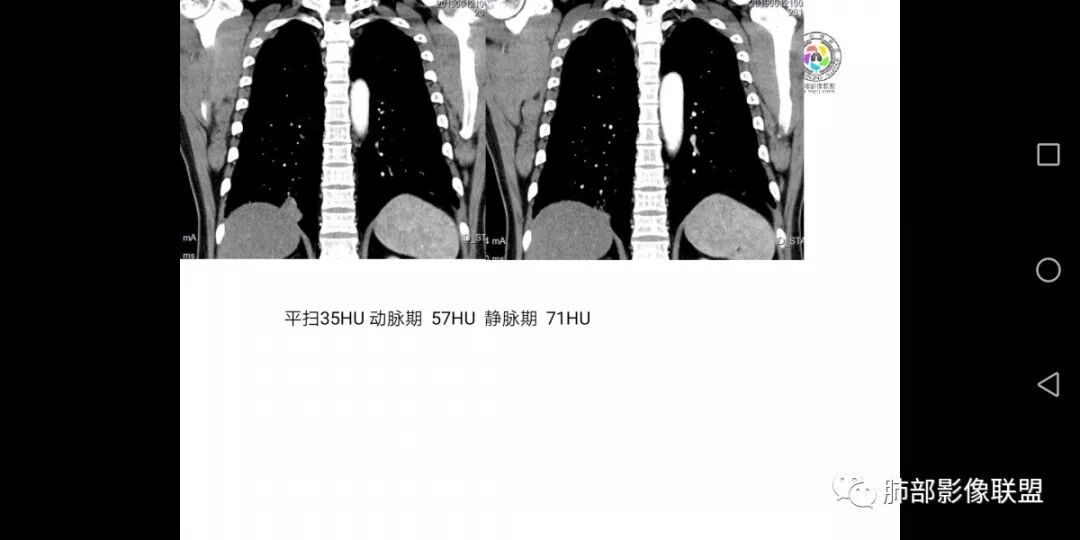

患者男,45岁,因乏力、低热、心悸入院,最高体温38℃,偶有咳嗽、无咳痰、咯血,肿瘤标志物阴性。

男,45岁;乏力、低热、心悸,38°,偶咳;症状像结核,但无钙化,无积液;三期:35-57-71偏心空洞,冠状位胸膜有牵拉力:需考虑鳞癌,男性,45岁,年龄偏小,吸烟史?

增强特点:多为明显强化,CT值增加40-80HU之间),一般很少出现深分叶、钙化及淋巴结肿大的特点,常可与周围性肺癌鉴别。